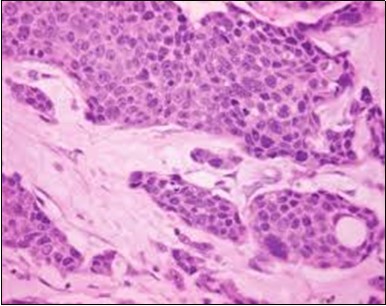

The neoplasm is composed of lobules of aberrant epithelial cells configured in cords with incrimination of the dermis and epidermis.. Malignant cells congregate within the epidermis or infiltrate the dermis, especially in the primary tumour. Tumour cells within tumour aggregates display a well demarcated cellular outline and appear distinct from encompassing squamous cells. Numerous tumour cell clusters demonstrate a cystic lumen. Prominent epidermal acanthosis is discerned on account of tumour cell proliferation 6, 7.

Figure 2.Epidermal projections lined with atypical and malignant epithelial cells in eccrine porocarcinoma (14).